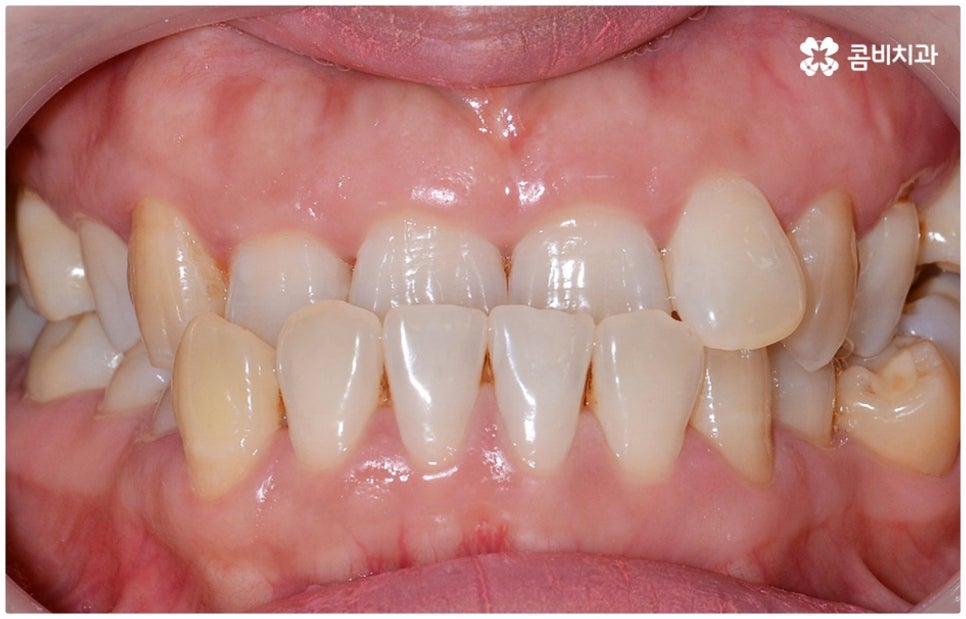

정상적인 교합은 윗 앞니가 아래 앞니를 살짝 덮는 정도로 윗니가 조금 더 앞으로 나와 있으면서 위아래 치아가 어금니까지 잘 맞물리는 것을 말하는데 반대교합은 위아래 앞니가 거꾸로 물리는 증상을 보이기 때문에 저작 활동 및 발음 조성이 원활하지 않게 되며 반대교합교정 등 적절한 치료를 받지 않고 방치할 경우 점점 더 주걱턱이 강화되는 쪽으로 뼈가 성장할 수 있어 될 수 있는 대로 빠른 시일 내에 원인을 분명하게 알아보고 그에 맞는 치료를 받는 것이 중요하다고 할 수 있어요.

골격적인 원인이 아니라면 위턱과 아래턱의 위치나 크기에는 이상이 없는데 치아의 맹출 각도 및 방향의 문제로 인해 치아가 반대로 맞물리게 된 치성 반대교합에 해당하는 경우라고 할 수 있는데요. 그 원인으로는 선천적인 치열의 문제 (아래턱 앞니 치축이 앞으로 기울거나 위턱 앞니 치축이 뒤로 들어감), 유치가 너무 빨리 빠지고 영구치가 자리를 제대로 잡지 못해 생긴 문제, 후천적인 습관 (혀를 내밀거나 손톱을 깨무는 등 치열에 좋지 않은 영향을 주는 행위를 지속적으로 반복) 으로 인한 문제 등등을 살펴볼 수 있으며, 보통 이런 경우 앞니 4~6개 치아 일부에 국한된 문제이기 때문에 보다 빠르고 간단하게 교정 치료가 가능하므로 꼭 성장기에 치료를 시작하지 않고 성인이 된 후라고 해도 비교적 쉽게 개선이 될 수 있습니다.

교정 치료가 생물학적 반응을 이용하는 것이다 보니 성장기에 진행하면 치아 이동 및 회복 속도 등에 장점이 있는 것은 분명하지만 그렇다고 해서 성인 이후 중장년 분들이 교정 치료를 받을 수 없는 것은 아니며 이미 많은 분들이 도움을 받고 계신 만큼 이에 대해서 한 번 고려해 보시면 좋을 거예요. 혹시 성장기 이후로는 양악 수술 등으로만 치료가 가능한 것이 아닐까 생각하셔서 부담스럽게 느끼셨던 분들이라면 지레 겁을 먹고 불편함을 그대로 방치하시기 보다는 검진 및 상담을 통해 적극적으로 이를 해결해 보시길 권유드리고 있어요.

물론 원인과 정도에 따라 외과적인 방법이 필요하신 분들도 있을 수 있지만 교정을 통해 얼마든지 치료가 가능한 경우도 있으며 앞서 말씀드렸던 것처럼 발전된 교정 기술 및 특수 미니스크류 등의 장치 개발을 통해 턱의 방향을 조금씩 회전시켜 원거리 치아 이동을 유발하는 것이 가능해졌기 때문에 예전에는 한계가 있었던 부정교합 케이스도 개선될 여지가 늘어나고 있습니다. 꼼꼼하게 검진을 받으시고 자신의 상황에 맞는 교정 치료를 무리하지 않게 진행하신 후 철저하게 사후 관리를 해주시면 보다 오랜 기간 동안 건강하게 고른 치열을 유지하면서 생활하실 수 있을 거예요.